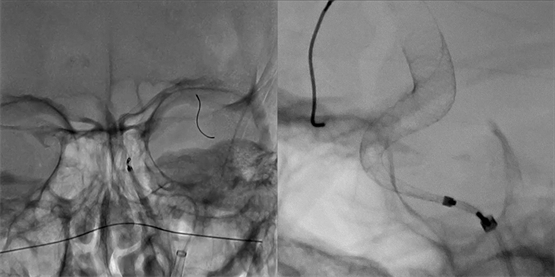

(复杂动脉瘤的Pipeline治疗)

复杂动脉瘤介入的难点在于血管解剖结构异常复杂、瘤颈宽大且边界模糊,操作空间极其有限,稍有偏差便可能造成破裂或分支血管受累,容错率极低。Pipeline治疗作为重建血流、封闭瘤腔的重要手段,对器械定位与贴壁判断的精度要求极高。然而在传统模式下(左图),影像层次灰暗、细节模糊,导丝与血管壁交叠不清,支架展开状态难以准确辨识。显微高清模式(右图)则以更高分辨率呈现血管壁、导丝、支架等微细结构,边缘锐利、层次分明,使支架贴壁与血流路径清晰可见。